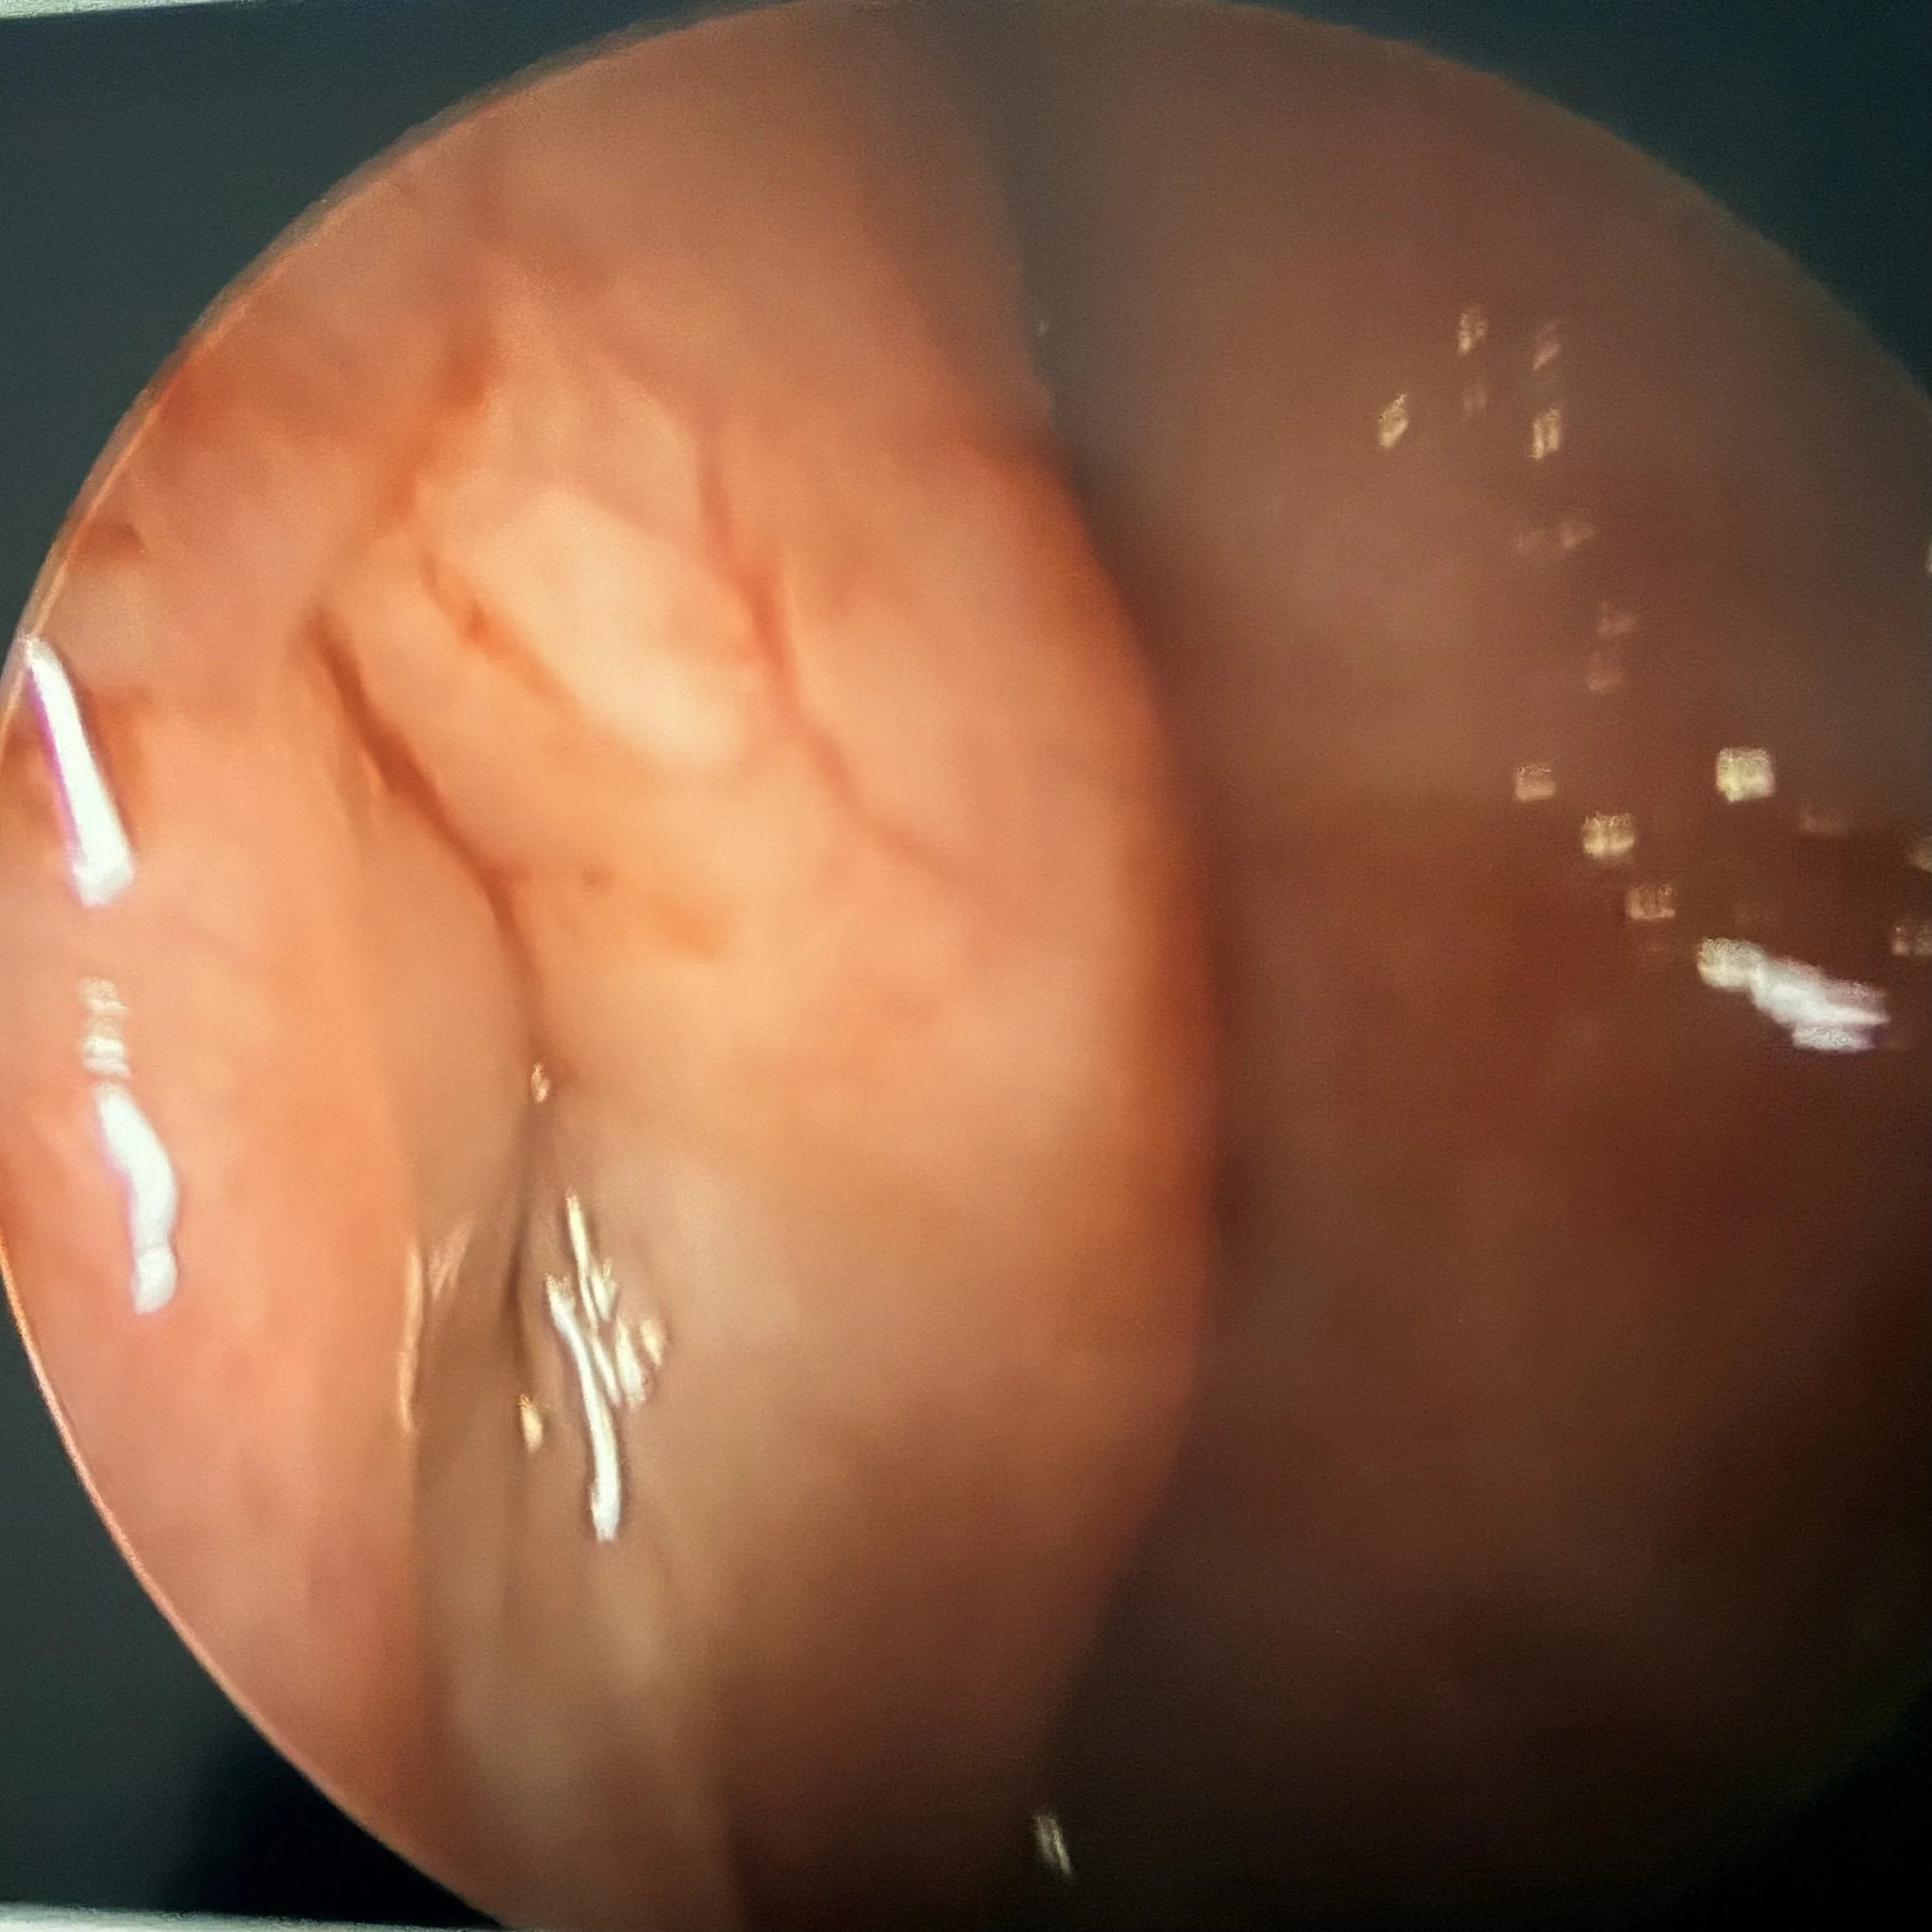

Before Surgery

Endoscopic view of intestinal lining showing smooth, pink tissue with some blood vessels and small protrusions.

Primary Pathology: The image demonstrates a Patulous Eustachian tube (PET), characterized by an abnormal, persistent patency of the tubal lumen at rest.

Anatomical Characteristics:

• Lack of Closure: There is a distinct longitudinal gap or cleft visible, indicating a failure of the normal mucosal closure between the anterior wall and the posterior cartilaginous cushion (torus tubarius).

• Patent Lumen: The pharyngeal ostium is visibly open, appearing as a dark, vertical fissure or "keyhole" defect extending into the cartilaginous portion of the Eustachian tube. Normally, this valve should appear as a tightly closed slit when at rest.

This persistent opening of the tubal valve is the classic anatomical presentation of a patulous Eustachian tube, which allows sound and air to travel freely between the nasopharynx and the middle ear cavity, leading to symptoms like autophony.